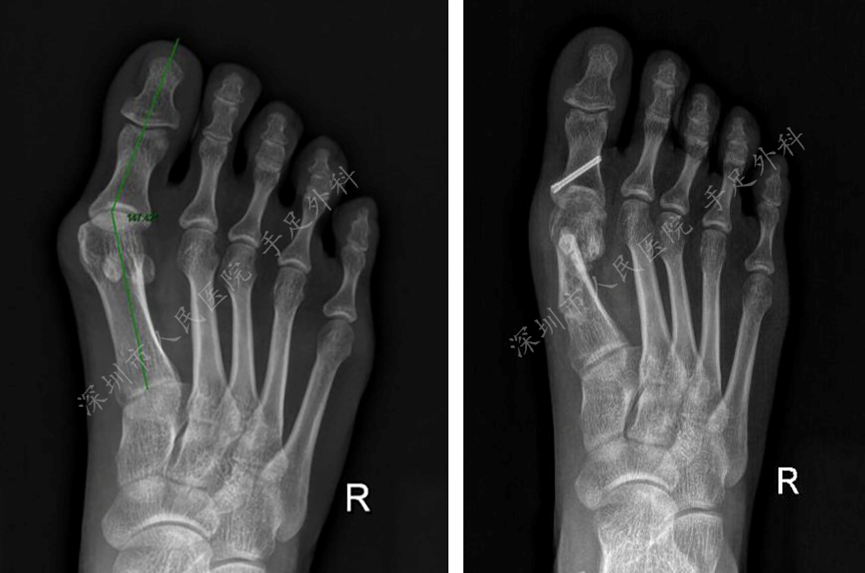

(二) 平足症

平足是指患者站立负重时,足内侧弓塌陷为主要表现的常见足部畸形,国内文献报道平足的发生率为3.7%-8%。本中心聚焦儿童及青少年平足症的矫正。

图6:跗骨螺钉置入是儿童柔韧性平足症的微创治疗技术,通过植入螺钉增强距下关节稳定性,改善足部功能。

图7:跗骨螺钉置入明显改善了足部功能。

图8:跗骨螺钉置入明显纠正了足跟外翻。